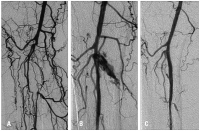

Ischämie

Abbildung 3a-b: A. Kritische Ischämie bei Verschluß des Truncus tibiofibularis. B. Nach Implantation eines Cypher 3,5/33 mm-Stents. C. 6-Monats-Follow-up.